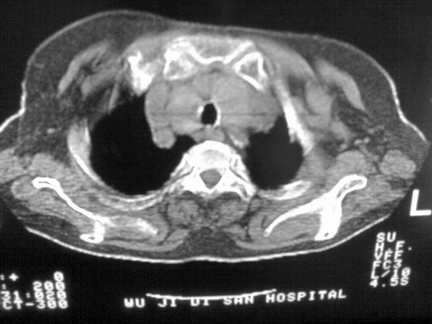

标题: CT13142:女 80 胸闷、气短、1w [打印本页]

标题: CT13142:女 80 胸闷、气短、1w

右肺炎性变,双侧甲状腺肿,胸膜肥厚。

右肺炎性变

双侧胸腔积液

缩窄性心包炎

作者: muzi888    时间: 2008-4-29 18:49

左室为主的心脏增大。

胸膜肥厚,

气管,支气管软骨钙化。

右肺感染;双侧胸腔少量积液,心影增大,可能与心功不全有关;胸内甲状腺肿。

右肺炎性变,双侧甲状腺肿,胸膜肥厚,心影增大考虑心功能不全.

胸内甲状腺肿;右肺感染;双侧胸腔少量积液。

胸内甲状腺肿;右肺中叶感染;双侧胸腔少量积液;心影增大,考虑有心功能不全。